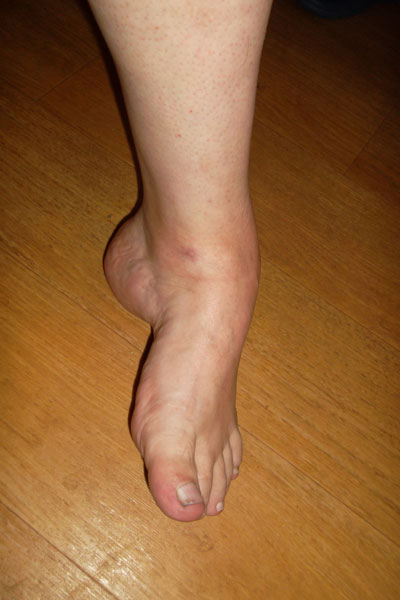

В 1992 году перенёс энцефалит, после этого левая стопа с годами начала деформироваться всё сильнее и сильнее. Последнее время стопа при нагрузки стала вывихиваться, появились ужасные боли, ходить становится всё труднее. Мне 42 года, в клинике Онипко мне поставили диагноз "Состояние после перенесенного энцефалита, эквино-поло-варусная деформация стопы, прогрессирующий подвывих голеностопного сустава в порочном положении, деформирующий артроз". 20 июля Н.Н. сделал операцию- артродез голеностопного сустава(остеосинтез компресирующим аппаратом Илизарова-Онипко. Швы сняли на 10-ый день, через 2 недели выписали домой.Фото до операцииФото до операцииФото до операции